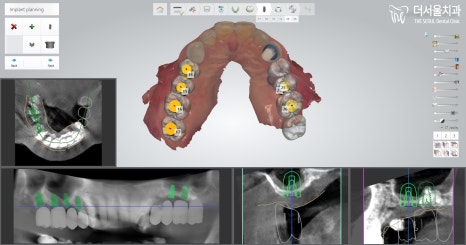

컴퓨터 분석을 이용하여

임플란트 식립을 어떻게 하면 좋을지

계획을 꼼꼼히 수립해나갔습니다.

곳곳마다 현재 가지고 있는 뼈의 양,

어떤 재료로 심어줘야 되는지,

골이식을 얼마만큼 해야 되는지,

미끌림은 없을지,

추가로 진행해야될 다른 진료는 없는지

꼼꼼히 확인 후 계획을 수립하였습니다.

첫 단추를 잘 꿰어야 된다는 말이 있듯이

치료를 함에 있어 좋은 결과가 있으려면,

꼼꼼히 정밀검사를 시행 후,

그에 맞게끔 계획을 짜놓는게 중요하죠.